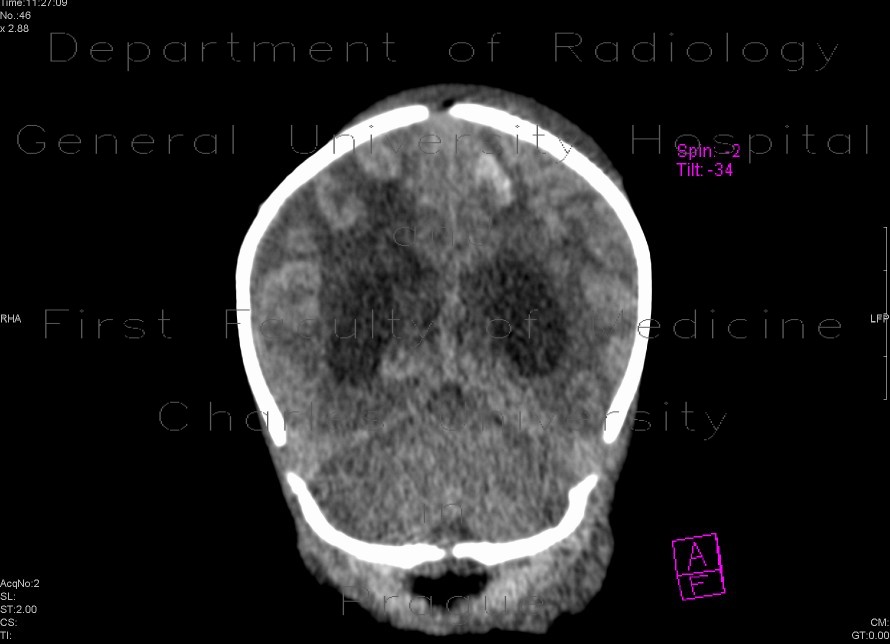

Meningencephalitis, abscessing

Severe meningecephalitis with oedema of brain parenchyma, markedly enhancing menings and an abscess formation in basal ganglia.

Radiology image - Meningencephalitis, abscessing: Brain, Brain: CT - Computed tomography